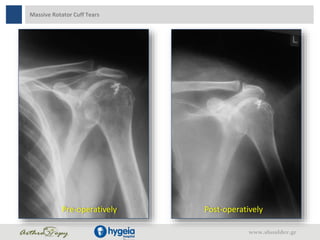

Massive Rotator Cuff Tears

Pre-operatively Post-operatively

Massive Rotator CuffTears Pre-operatively Post-operatively www.shoulder.gr